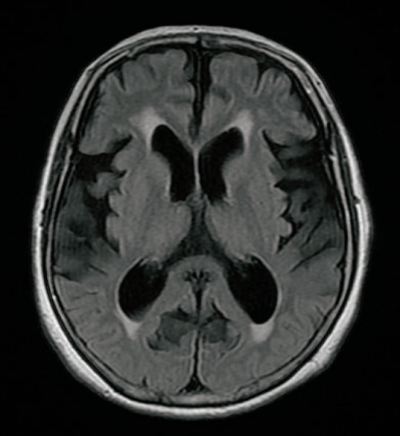

意識はJCSⅠ-2。体温 36.5 ℃。脈拍 86/分、整。血圧 142/88 mmHg。呼吸数 14/分。SpO₂ 97% (room air)。Mini-MentalState Examination〈MMSE〉23点(30点満点) 。頭部MRIのFLAIR水平断像及びT1強調冠状断像を別に示す。